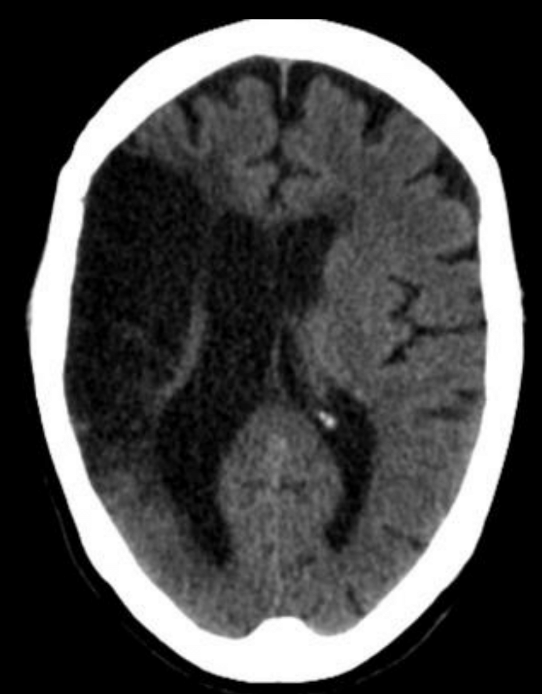

¿Qué fase es?¿Porqué?

Subaguda

Por la hipodensidad del edema